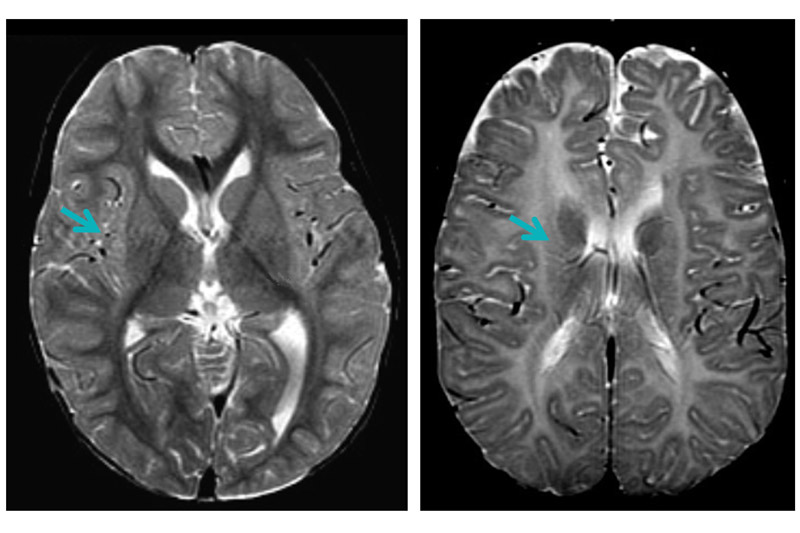

Conducted in four boys under the age of five with a severe form of PMD, their initial Phase 1 trial aimed to test the long-term safety of this procedure and, using brain imaging, to evaluate whether the transplants led to any changes in myelination. The investigators reported no adverse effects of the transplant 12 months following the procedure and observed changes on detailed MRI brain scans suggesting that myelination had occurred in the areas of transplantation.

In Stem Cell Reports, Gupta and Rowitch have now published a five-year follow-up on their stem cell implantation trial, reporting minimal adverse effects in the four subjects. The study also confirms that MRI changes consistent with myelination persisted in two of the four patients in the study. However, two of the patients exhibited immunological reactions to the neural stem cells, suggesting that immunosuppressive therapies may be required for future studies in order to prevent rejection.